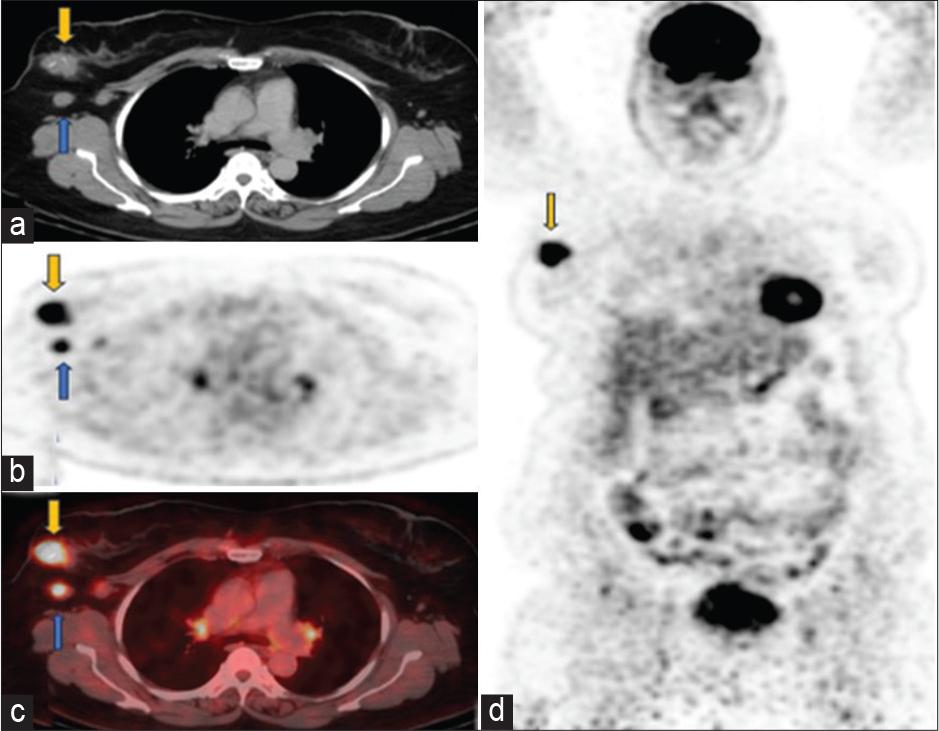

Figure 1: